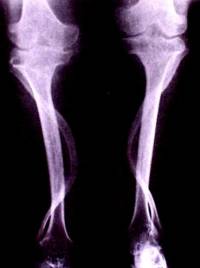

Reumatoidni artritis

Reumatoidni artritis (RA) je teška, kronična, upalna bolest vezivnog tkiva koje se najviše očituje na zglobovima. U ovom poremećaju imunološki sustav napada hrskavično tkivo, kosti i, ponekad, unutarnje organe. Od zglobova su najčešće zahvaćeni mali zglobovi šake, zglavci, ramena, koljena i gležnjevi. Oboljenje uzrokuje invalidnost koja značajno skraćuje životni vijek. Međutim, uz odgovarajuće zdravstvene mjere i izmjene životnog stila, oboljeli mogu imati dug i kvalitetan život.